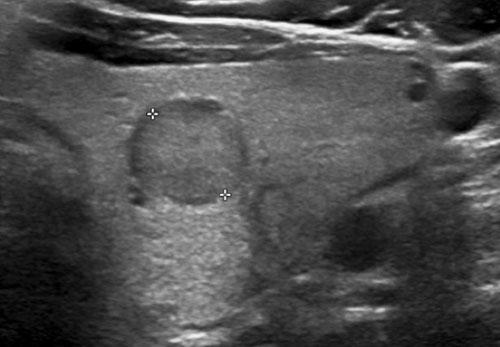

Trường hợp 3

Quan sát hình ảnh và xác định điểm TI-RADS.

Cuộn hình ảnh để xem điểm TI-RADS.

Trường hợp 4

Nốt này có thành phần đặc chủ yếu.

Thành phần nang tối thiểu, tương ứng 2 điểm cho cấu trúc.